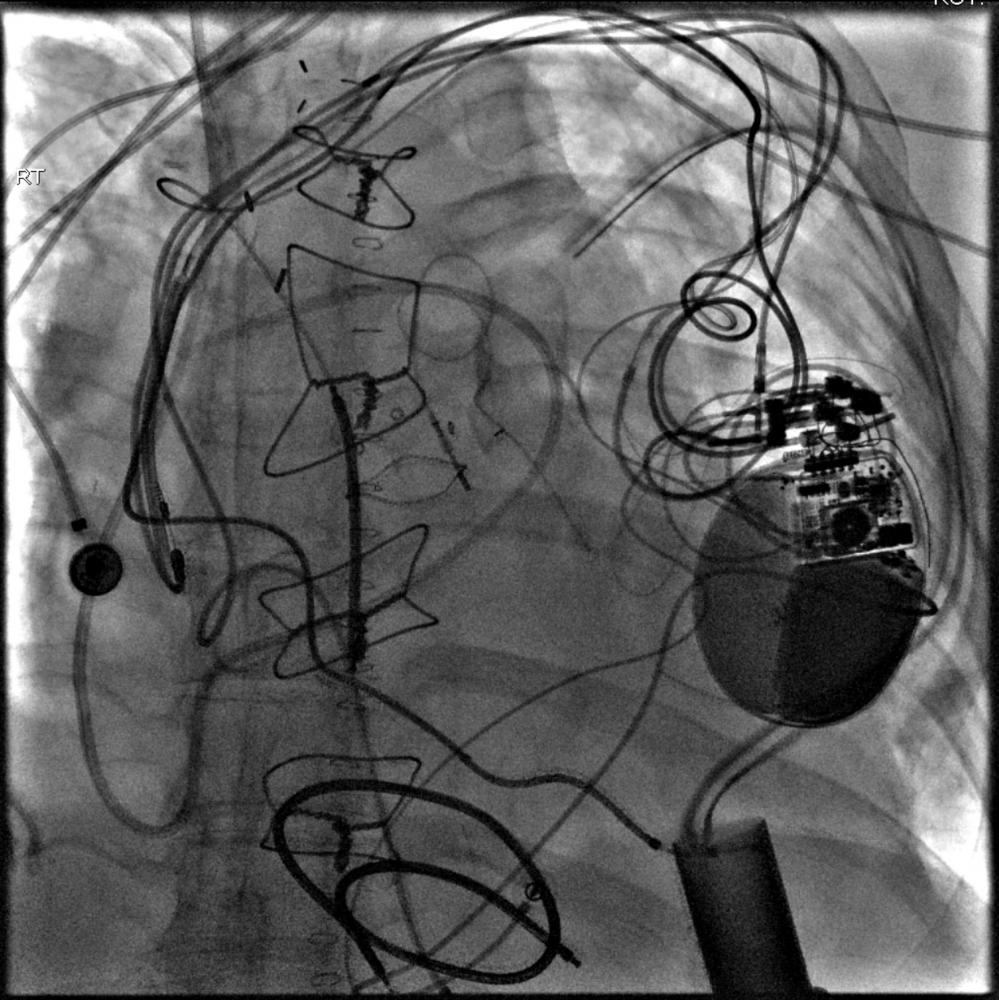

7. A left-sided approach often causes the tip of the venous access device to curve to the patient's left, necessitating a relatively wide SWEET SPOT™ design. See Fig.# 10 - Gallery.